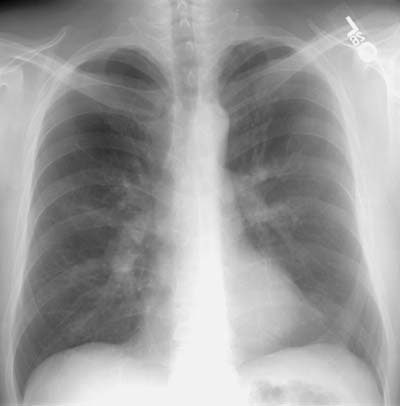

CXR demonstrated prominent central vascular shadows: